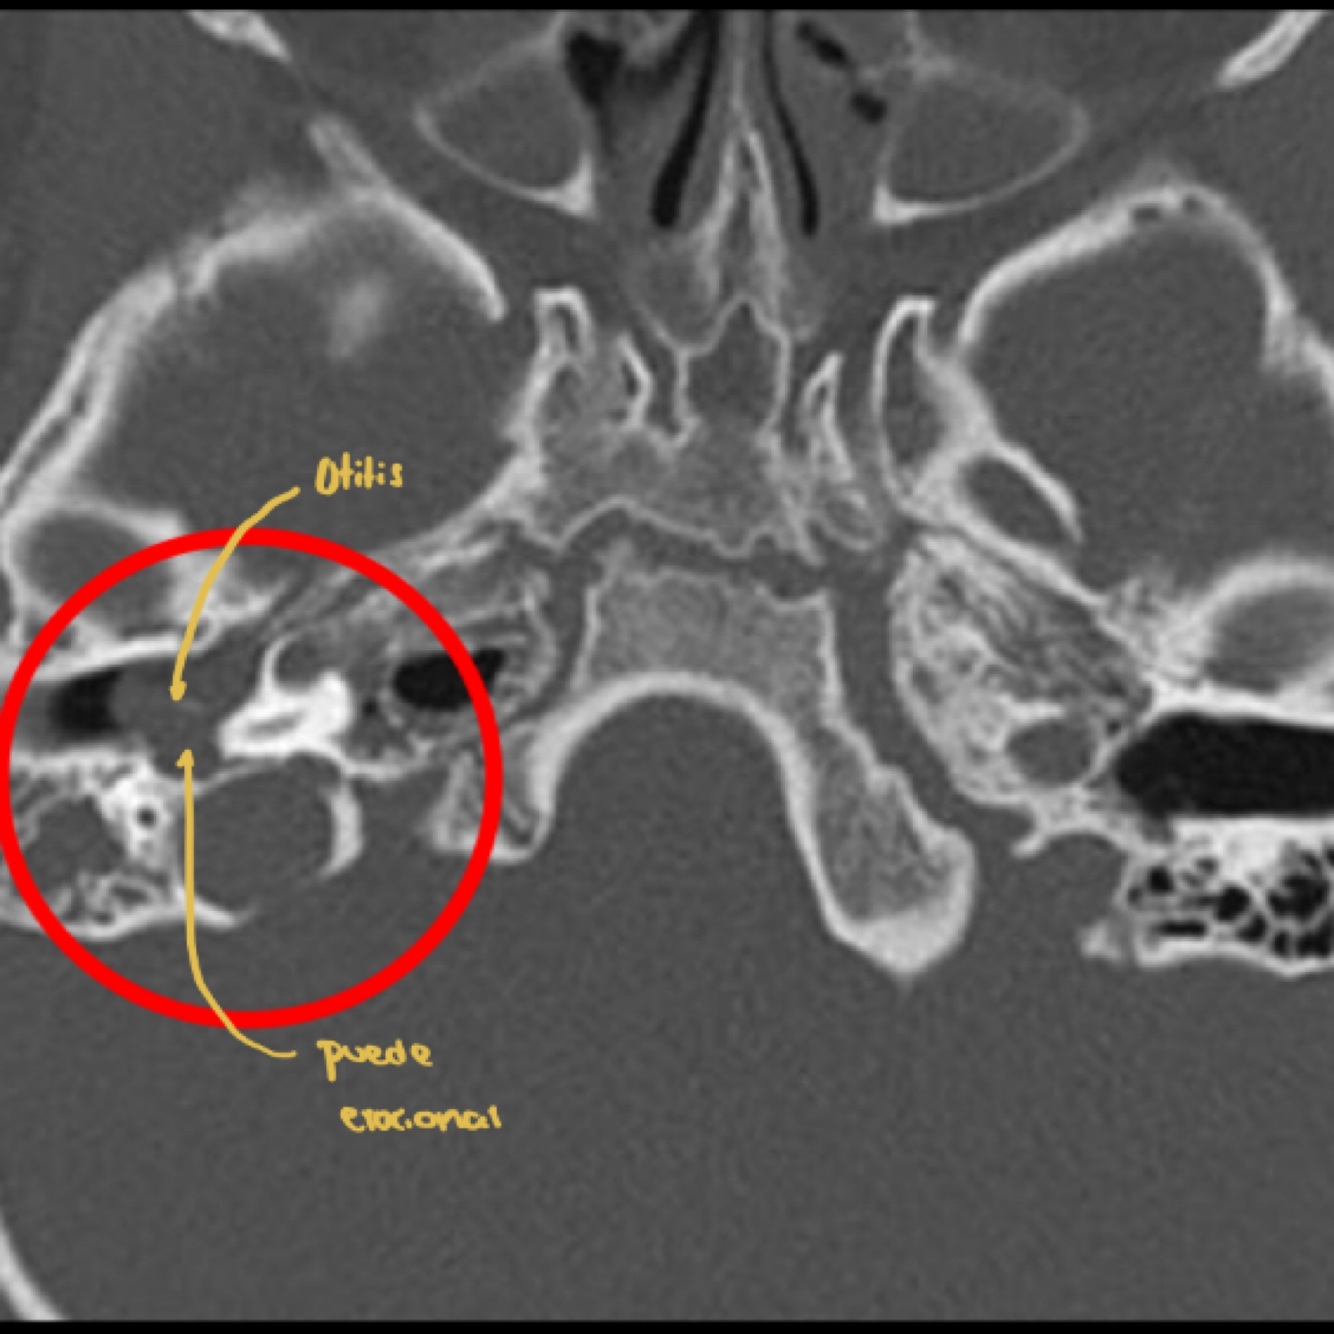

5

Q

Cuál es tu diagnóstico?

A

Otitis media

10

Clave en imagneología para dx de mastoiditis

Opacificación de celdillas mastoideas+ colección de líquido (pus o moco)

Si es crónico vemos efecto esclerodiploico que es mastoides osificada